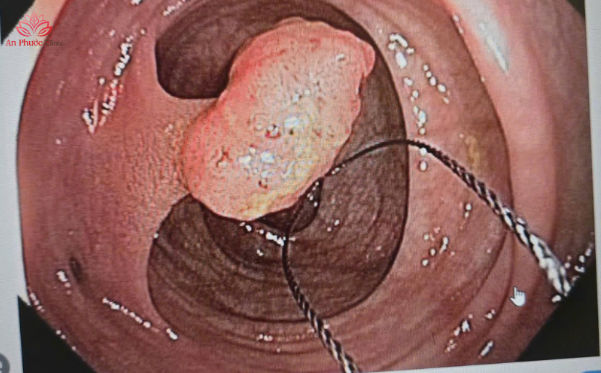

Bước 3: Cắt polyp (Polypectomy)

Nếu phát hiện polyp, bác sĩ sẽ luồn dụng cụ chuyên dụng qua ống nội soi để cắt bỏ khối polyp và cầm máu ngay lập tức. Quá trình này diễn ra nhanh chóng, bệnh nhân đang trong trạng thái tiền mê nên hoàn toàn không cảm thấy đau đớn.